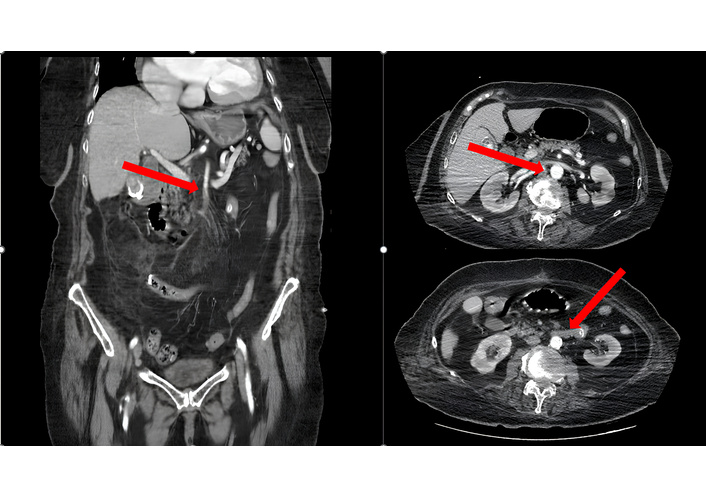

An 86-year-old female presented to the emergency department with sudden-onset severe abdominal pain accompanied by nausea and vomiting. She had a history of atrial fibrillation, hypertension, diabetes, and hyperlipidemia, and had undergone coronary stent placement five days earlier. On physical examination, the abdomen was distended, bowel sounds were hyperactive in the right lower quadrant, and diffuse abdominal tenderness with guarding was noted. Rectal examination revealed normal. Initial abdominal ultrasonography did not demonstrate any specific pathology but revealed the presence of free intraperitoneal fluid. Subsequent contrast-enhanced abdominal CT angiography showed restricted flow in the superior mesenteric artery (SMA) and edematous small bowel walls. To further clarify the etiology of the intra-abdominal fluid, ultrasound-guided paracentesis was performed, yielding turbid, serous fluid with a broth-like appearance, raising a strong suspicion for advanced intestinal ischemia. The patient’s contrast-enhanced abdominal CT angiography findings are shown in Figure 1.

Contrast-enhanced abdominal CT angiography demonstrates paired perfusion of the superior mesenteric artery and edematous small bowel loops consistent with acute mesenteric ischemia. Red arrows indicate the areas of vascular compromise and bowel wall abnormalities suggestive of intestinal ischemia.